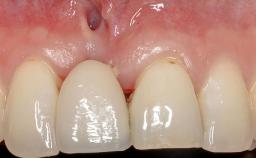

Early Implant Placement, Contour Augmentation, and Autologous Connective-Tissue Graft Using a Tunneling Technique to Replace an Upper Incisor with Generalized Gingival Recession

Variations in soft-tissue volume, evidenced either by an overabundance (Evian and coworkers 1993; Levine and McGuire1997; Dolt and Robbins 1997) or by a deficiency of soft or hard tissue can complicate implant-supported rehabilitations in the esthetic zone (Lorenzana 2008; Lorenzana and coworkers 2009). The present case illustrates the replacement of a failing upper left lateral incisor complicated by generalized severe gingival recession in the esthetic zone.

| Soft Tissue Contour and Volume | Significantly deficient |